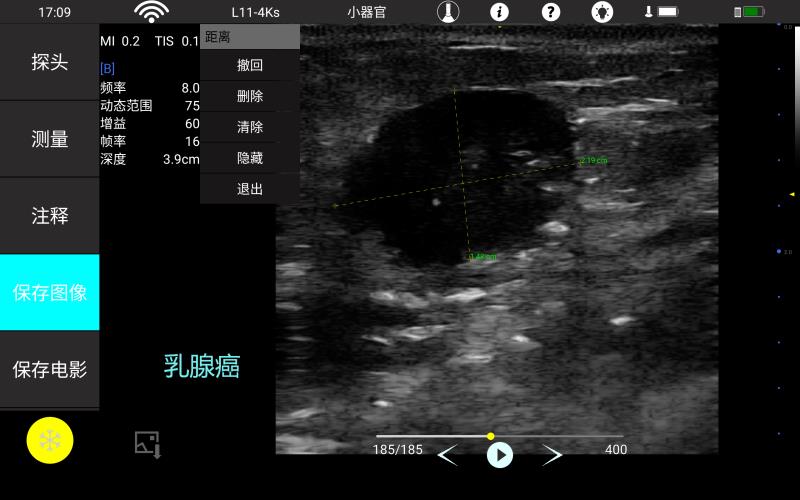

• 线阵

血管

神经

肌骨等